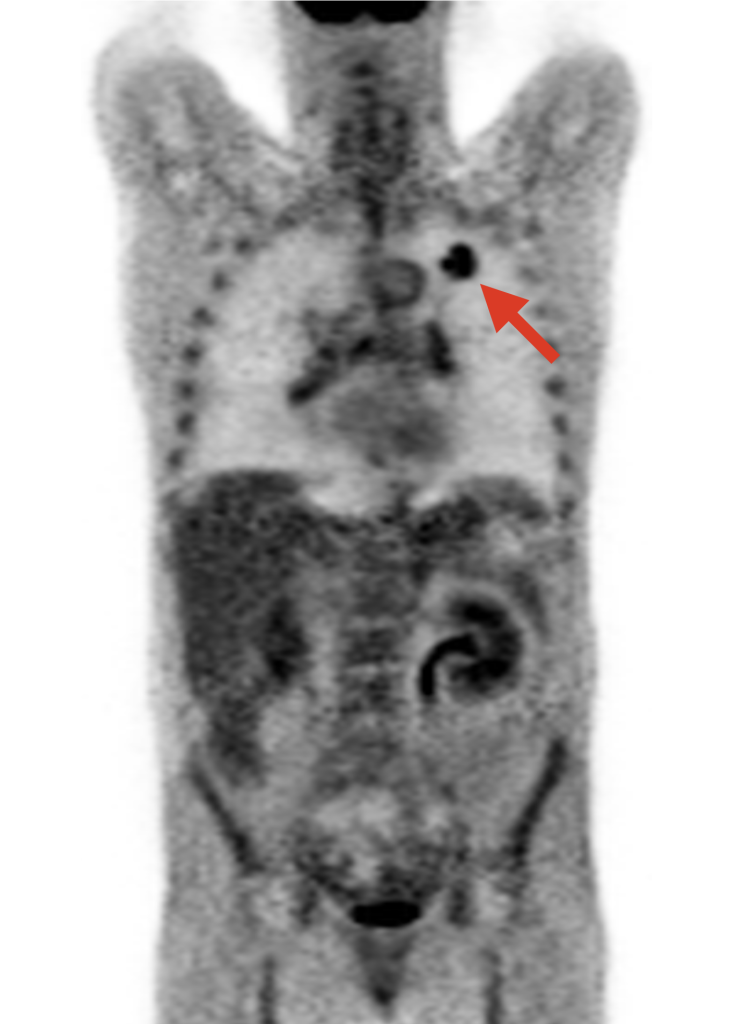

Cuando un paciente es diagnosticado de cáncer habitualmente se le somete a una prueba de imagen conocida como tomografía por emisión de positrones (PET). Esta técnica es un tipo de imagen metabólica, porque permite visualizar los procesos metabólicos que existen en las células [2]. Para tomar una imagen PET se comienza por inyectar en el cuerpo del paciente una sustancia análoga a la glucosa llamada FDG que tiene adherido un isótopo radiactivo (flúor {}^{18}\mathrm{F}). Esta glucosa modificada se distribuye por el cuerpo del paciente a través de la sangre y se dirige a las zonas que tienen un consumo preferente de la sustancia. Una de estas zonas son los tumores malignos, que tienen una gran avidez de glucosa debido a que la utilizan para mantener activos sus procesos de proliferación.

Después de un tiempo breve, los isótopos radiactivos que están adheridos a la FDG se descomponen y cada uno de ellos emite una partícula subatómica que se conoce con el nombre de positrón. Los positrones emitidos interaccionan con la materia circundante generando una señal que puede detectarse en un tomógrafo en el que está colocado el paciente. Esta señal se utiliza entonces para reconstruir de manera precisa los lugares en los que se ha emitido y cuánto de intensa ha sido la emisión, lo que es proporcional a cuánta glucosa había en una zona en particular. El resultado se traduce en una imagen tridimensional en escala de grises, que visualiza qué zonas internas del cuerpo están consumiendo glucosa y en qué medida. Cuanto más negro se ve, mayor es el consumo. En la siguiente imagen (Figura 1) se aprecia un corte concreto (la imagen completa es en 3D) de un estudio PET en un paciente con cáncer de pulmón.

En estas imágenes el tumor se visualiza claramente, lo cual es muy útil para los médicos. Lo interesante para los matemáticos es que estas imágenes contienen datos estructurados espacialmente que informan de qué zonas del tumor están consumiendo más o menos glucosa y dónde se encuentran localizadas (Figura 2). El nivel de escala de gris que se visualiza en la imagen representa normalmente una medida de consumo de glucosa que se llama Standardized Uptake Value (SUV). Zonas con alto SUV corresponden a zonas de alta absorción de glucosa (correspondientes, como hemos dicho, a zonas con gran proliferación celular) y se visualizan de color negro. De manera correspondiente, zonas blancas o con gris muy suave son zonas en las que no hay gran captación (bajo SUV). En general, encontramos que distintas zonas del tumor tienen distintos niveles de captación, ya que el cáncer es una enfermedad muy heterogénea.